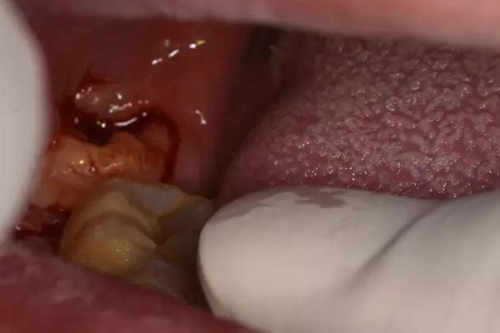

圖5.探針分離牙齦

圖6.半閉口,牙挺放置在48近中、采用推法、挺法、撬法拔除48,48松動半脫位